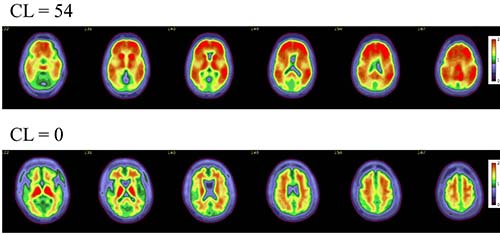

Axial color scales images of two brains show examples of an amyloid positive scan with a higher centiloid (CL) number and more red colors compared to a normal scan with normal background binding of the amyloid tracer signifying no amyloid plaques.